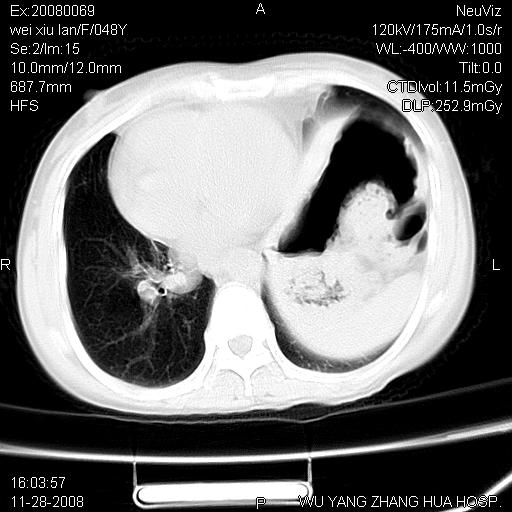

标题: CT16847:女,48岁,咳嗽,发热两日,平常偶有上腹部不适。 [打印本页]

标题: CT16847:女,48岁,咳嗽,发热两日,平常偶有上腹部不适。

能否考虑食管裂孔疝?请老师们多多指教。

这个是左侧膈膨升伴不完全性胃翻转,手术将松弛的左横膈膜折叠缝合即解决问题。

支持左侧膈疝,心脏受压右移.

左下肺不张、膈膨升,胸腔胃

2.左下肺炎性改变

胃、脾脏及部分肠管明显升高,并压迫心脏移位,

首先考虑:左侧膈疝。

左侧胸腔内见胃肠及脾脏影

支持膈疝

左膈顶及肋膈角均上移,膈面光滑,考虑左膈肌麻痹